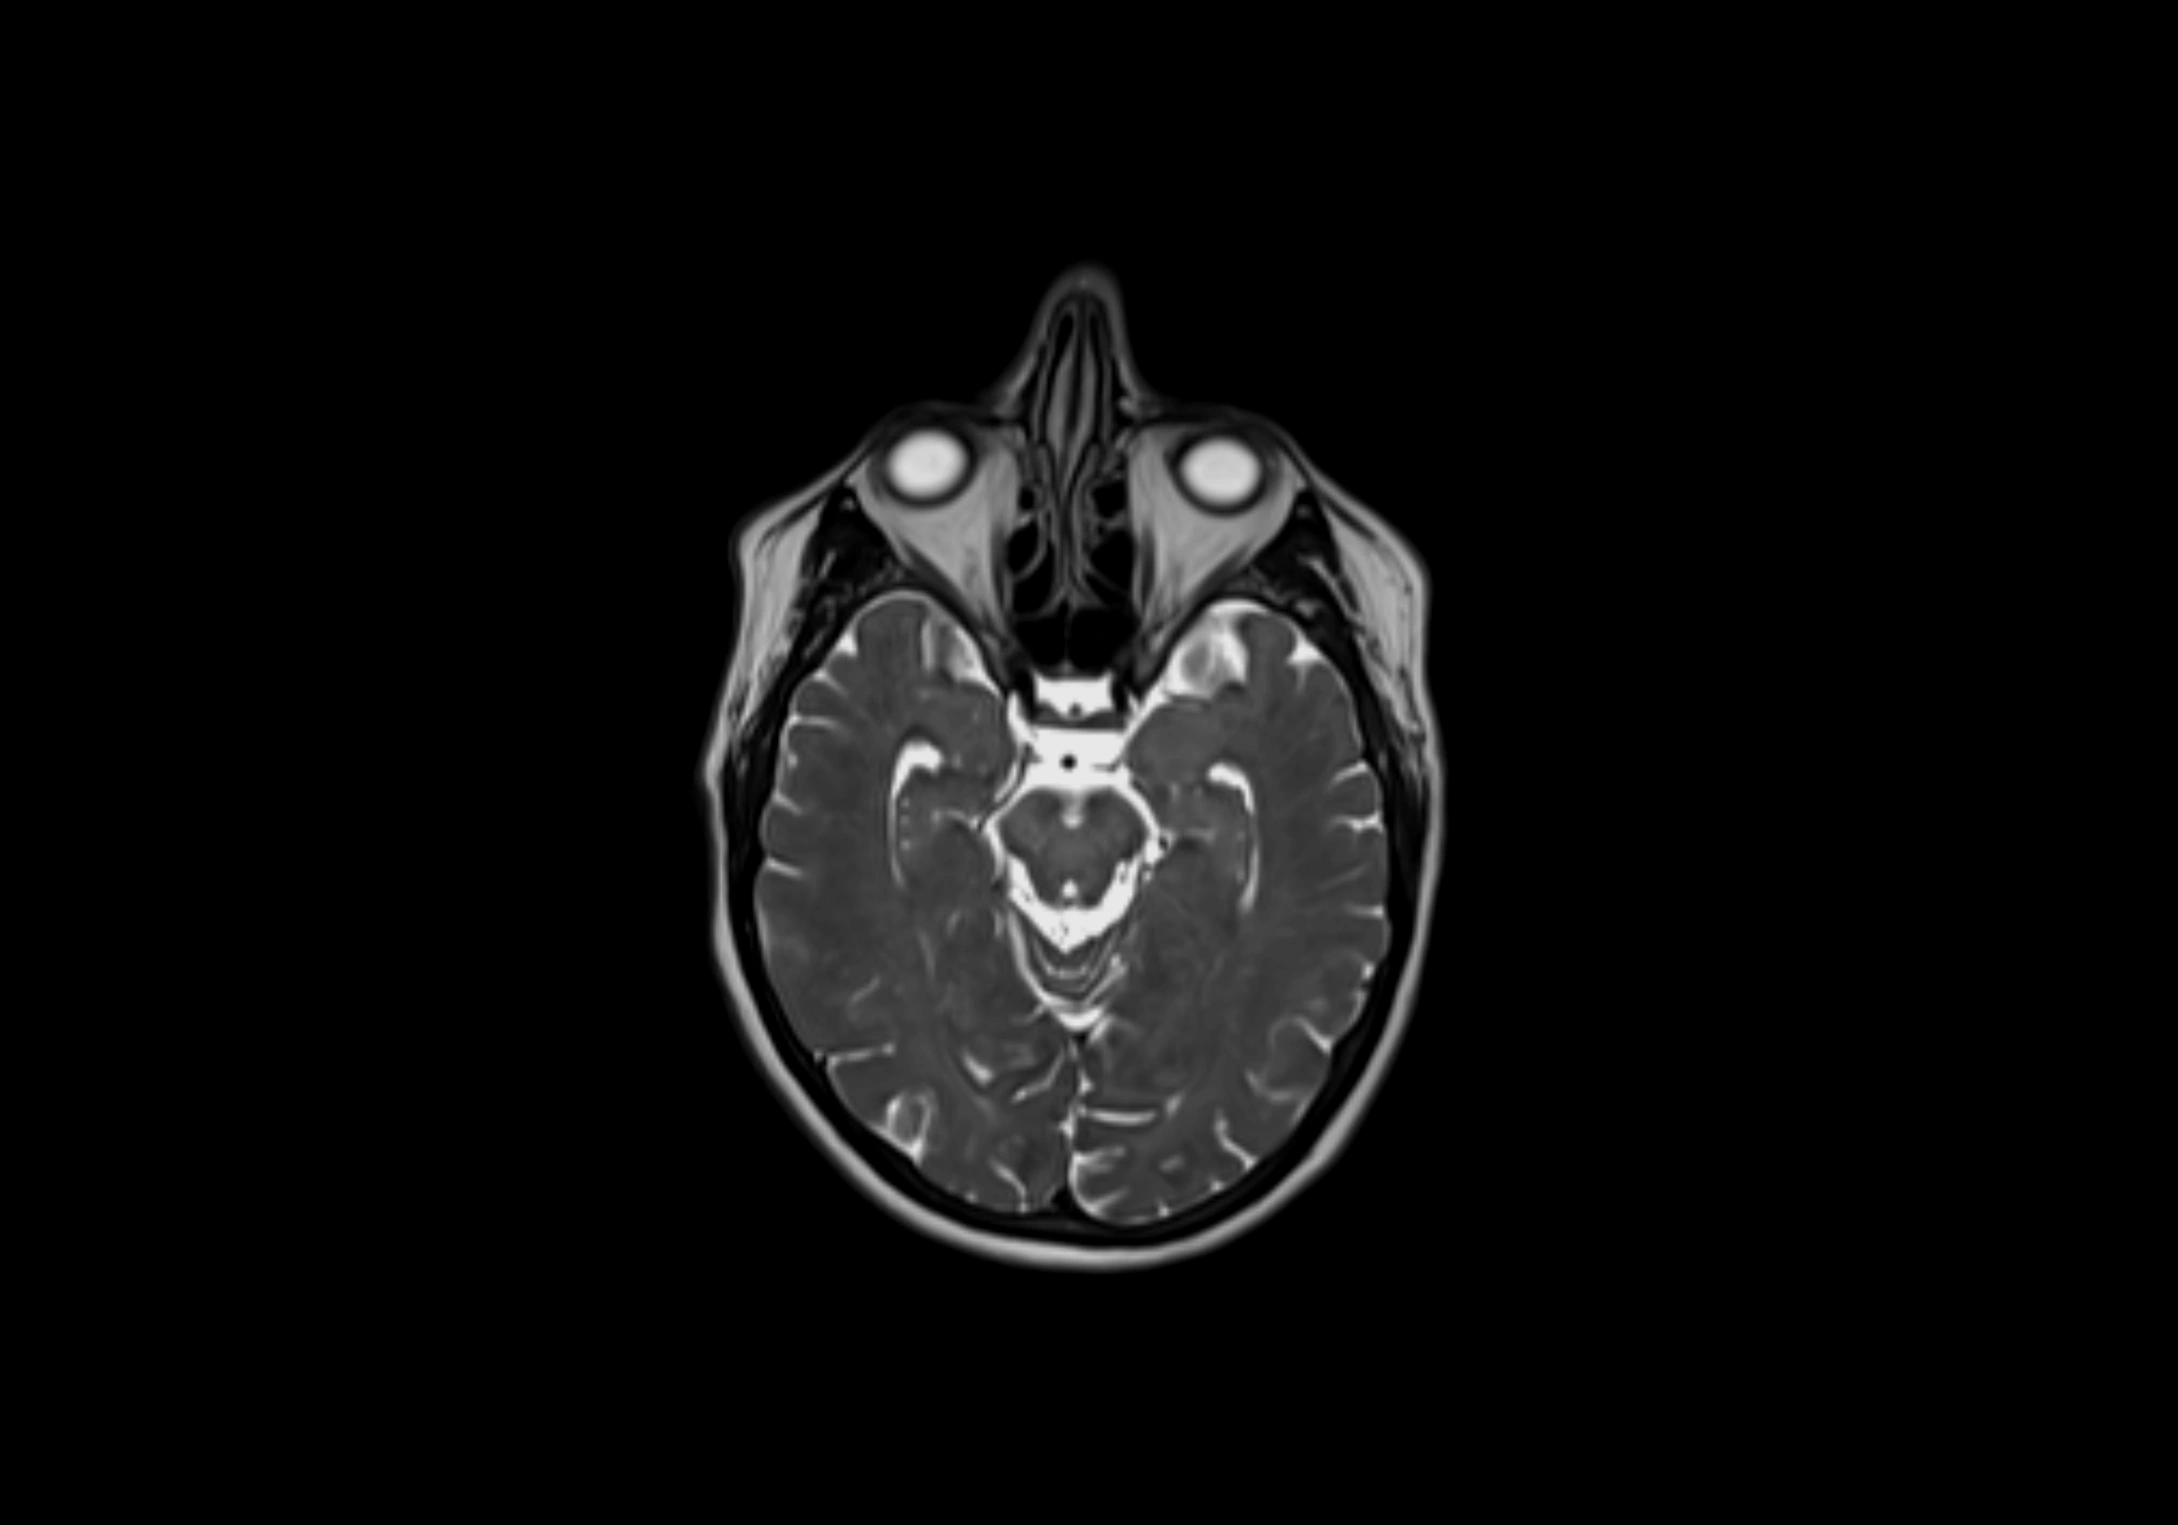

MRI Appearance

T2-weighted images:

• Nodes show intermediate signal, with surrounding fat bright

• Useful for detecting edema, inflammation, or infiltration

• Fatty hilum may appear slightly hyperintense relative to cortex